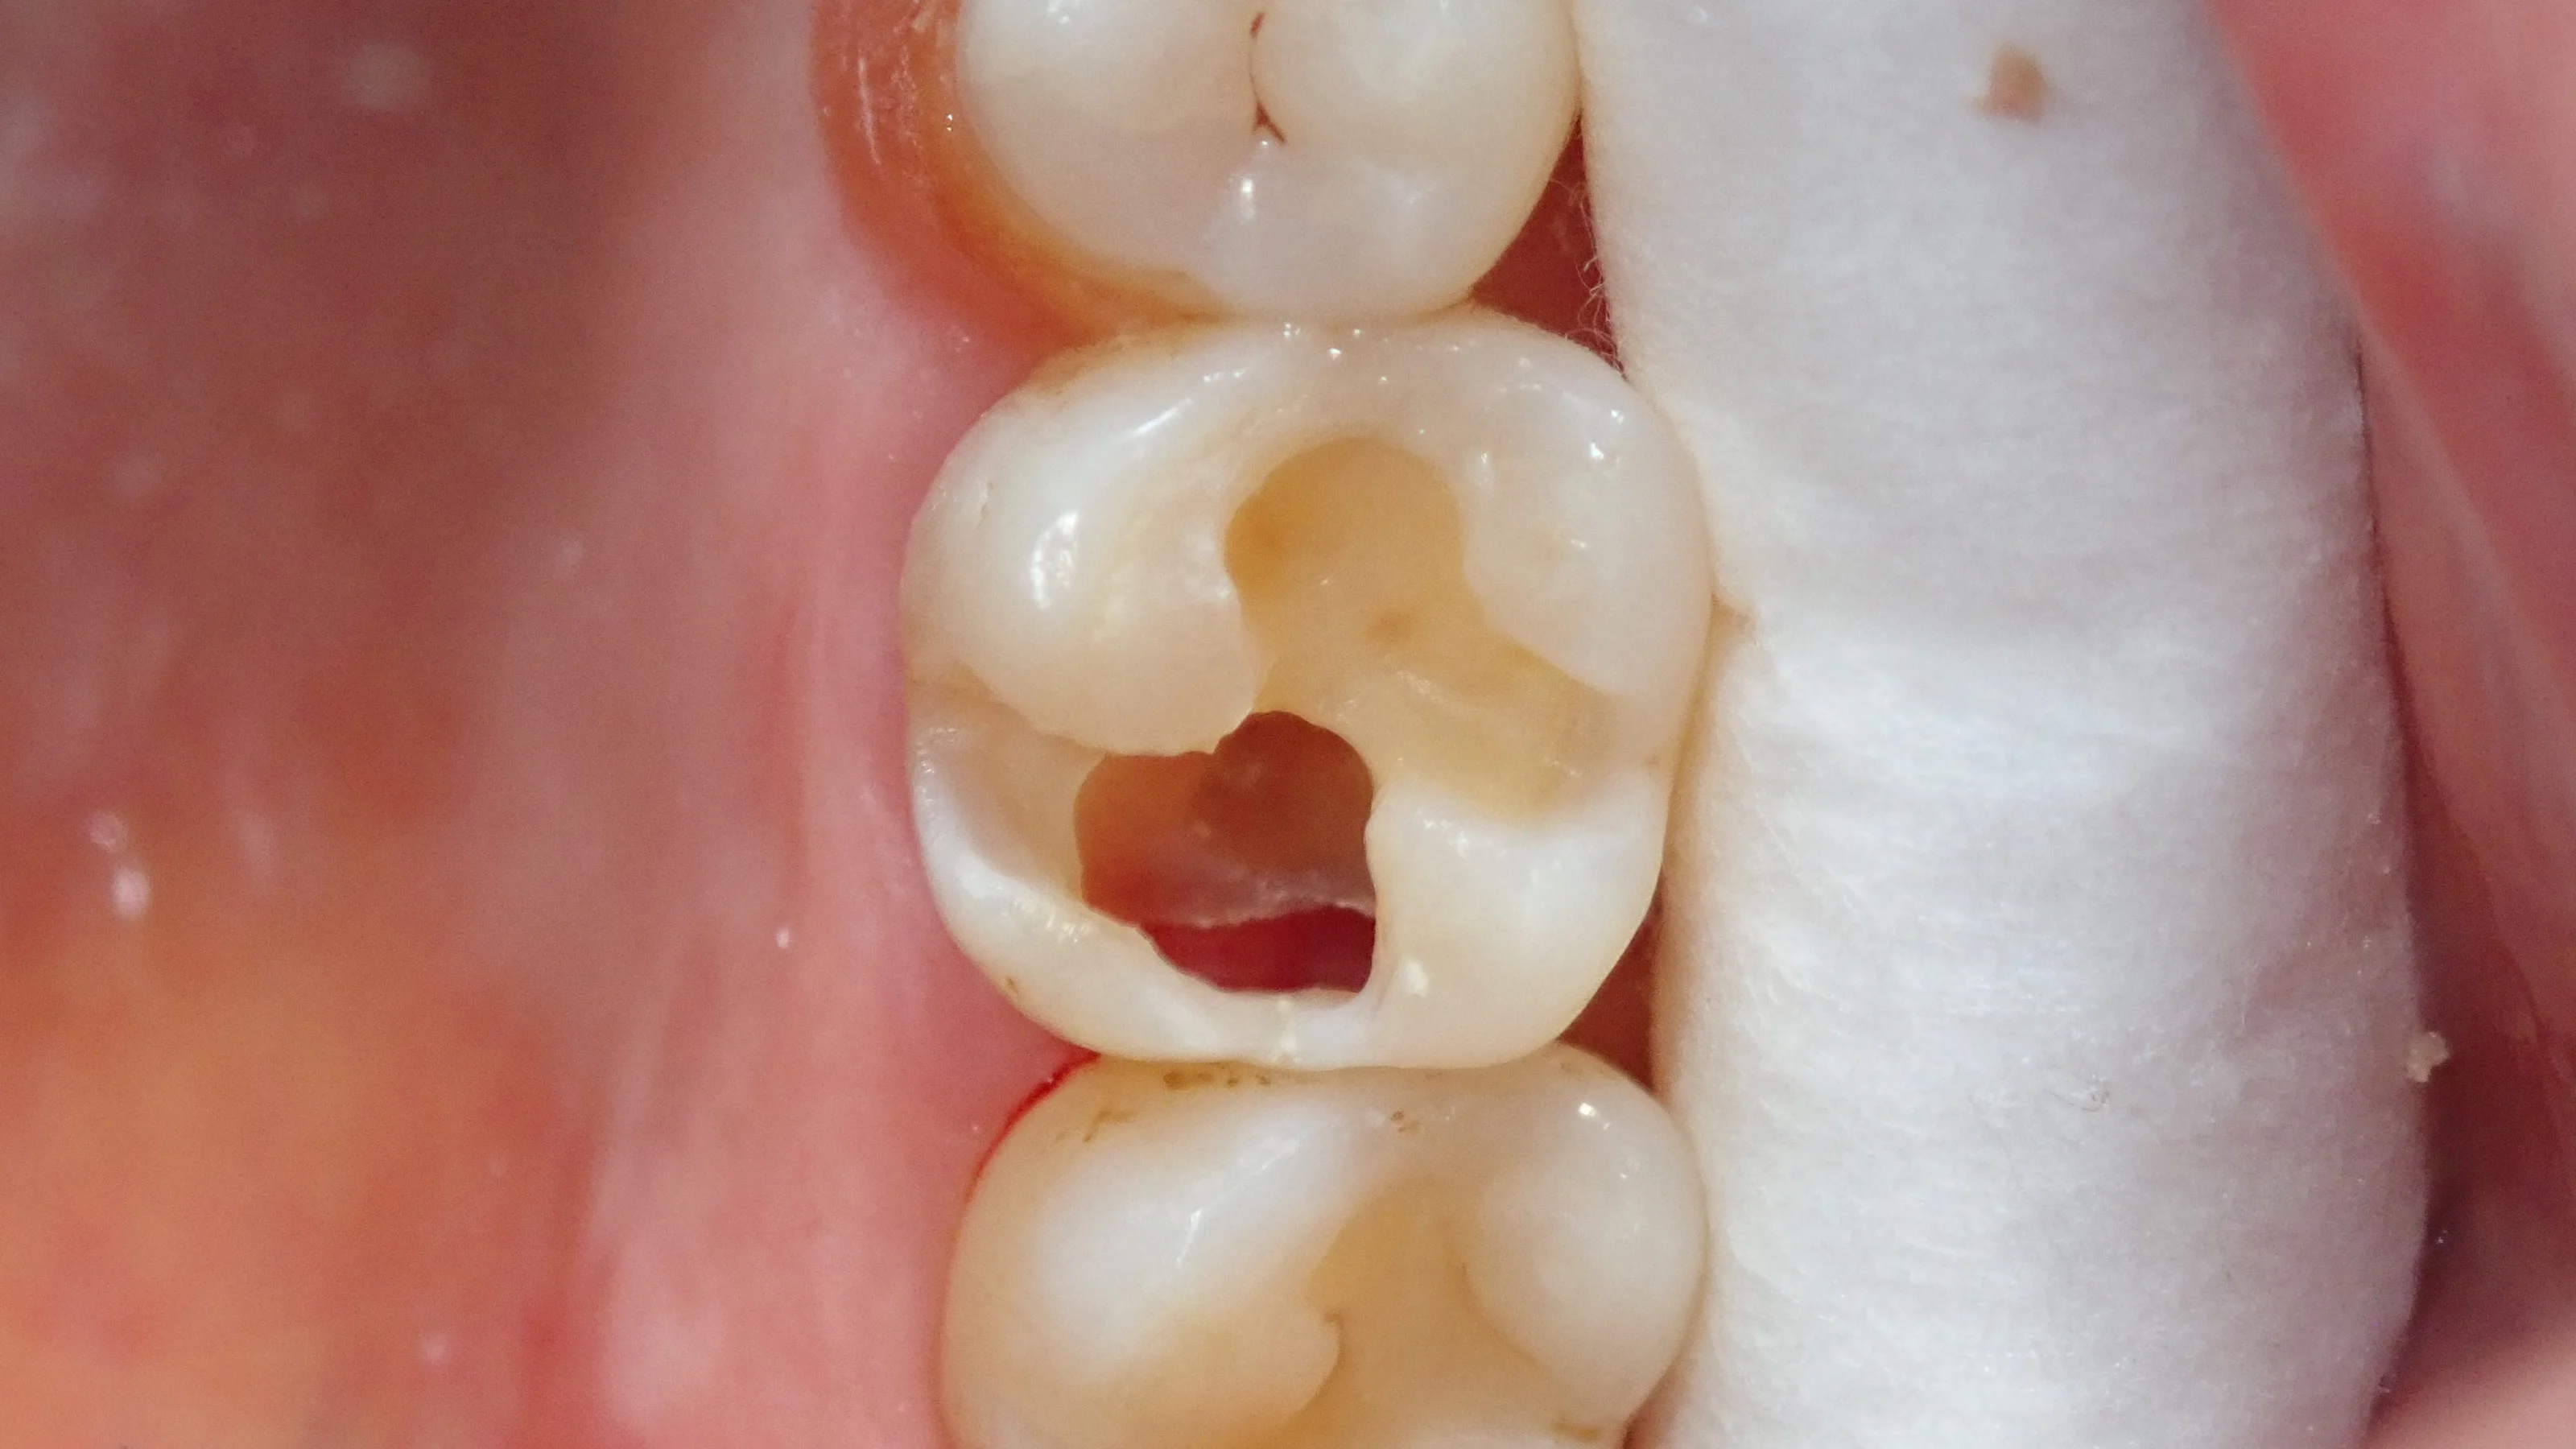

そして、仮封材を除去した画像がこちらです。

実際、画像の下半分は中身が殆どない状態です。

神経もうっすら見えており、歯茎が虫歯の穴から見えている状態。

本当にギリギリの状態だったんです・・・。